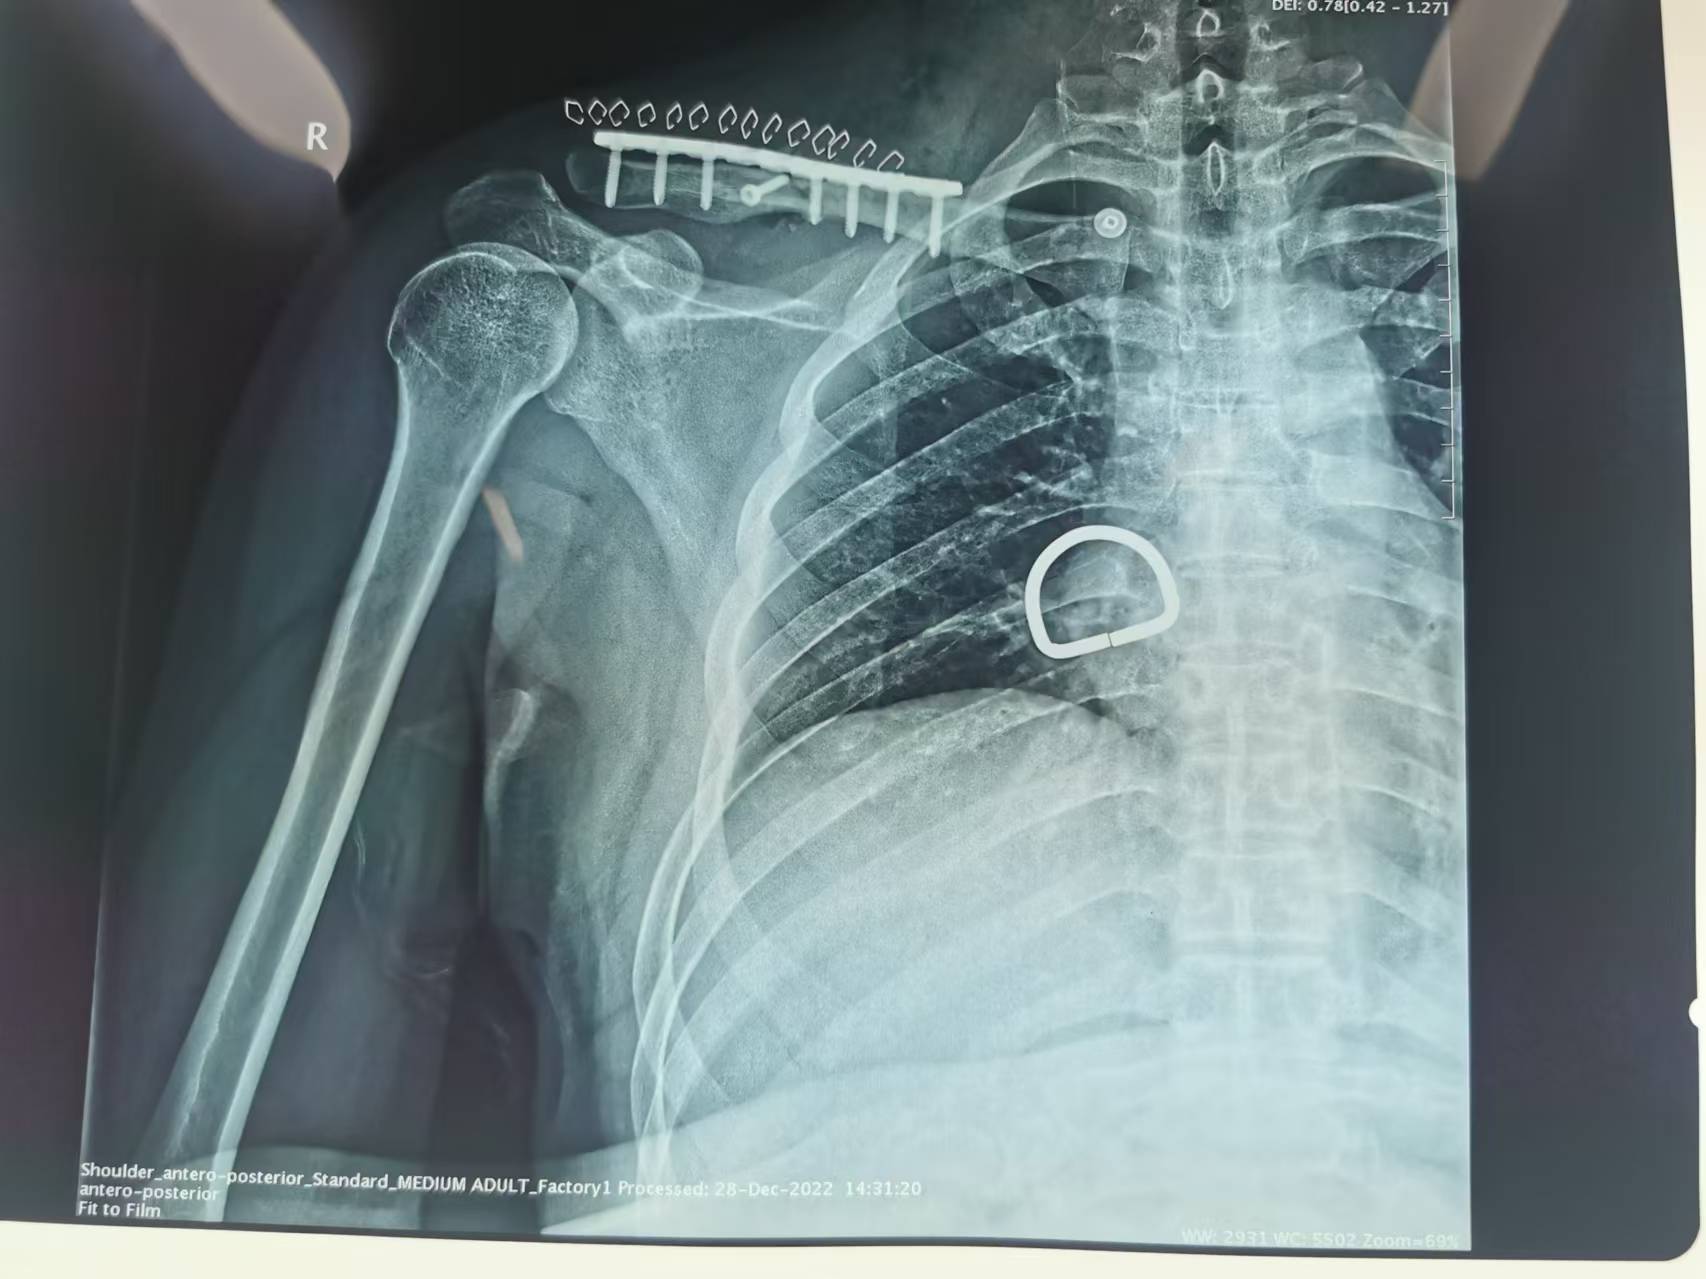

首页 > 张恒云工作室 > 影像资料 六